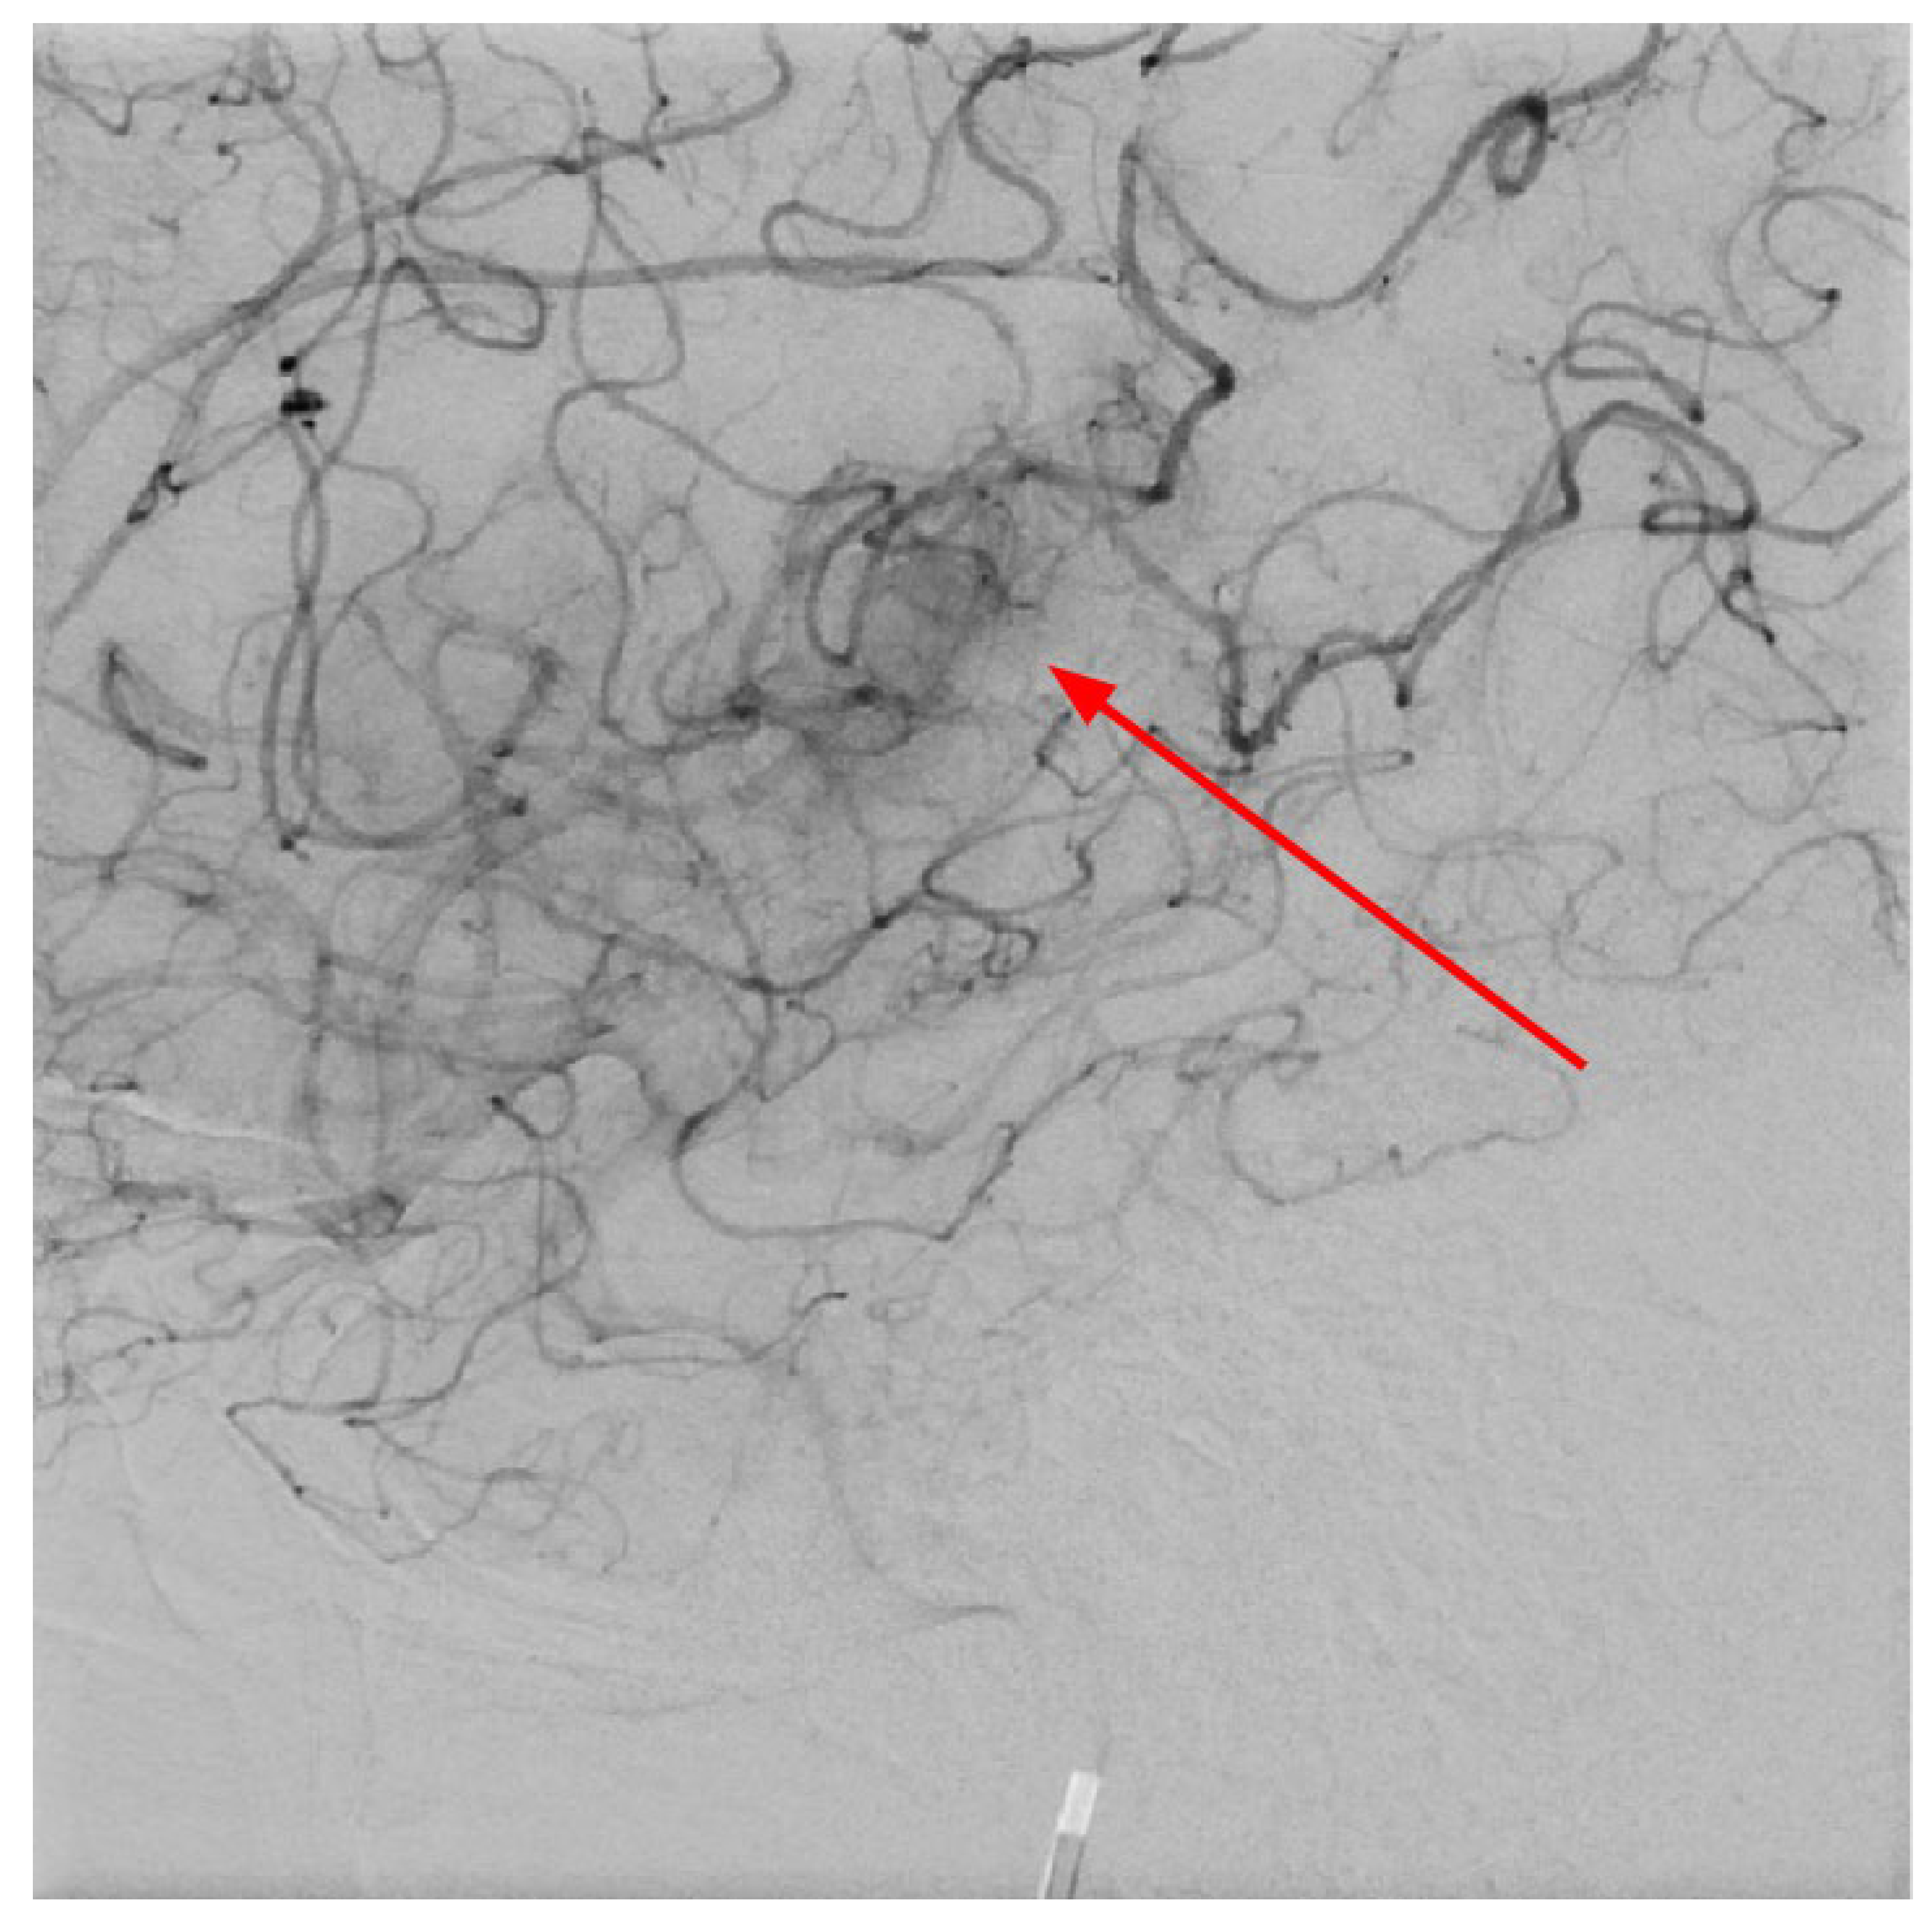

Figure 7. Digital subtraction angiography in LL projection at the level of basal ganglia showing abnormal vessels, which corresponds to developmental venous anomaly- venous angioma in the left area of the basal ganglia, also these changes seen on CTA and MRI after contrast injection (red arrow).

The next day, a neuroradiologist reviewed a control followup NECT, that demonstrated an ischemic lesion localized to the left insula, predominantly involving the left parietal lobe and the superior gyrus of the left temporal lobe (Figure 1). Additional radiological findings included a hyperdense artery sign, characteristic of acute thrombosis, and basal ganglia calcification on the left side, warranting further investigation to clarify the underlying aetiology. Subsequently MRI of the brain was conducted, which also revealed ischemic signs, as well as unilateral basal ganglia calcification (Figure 6). Digital subtraction angiography (DSA) was performed to clarify reasons for unilateral basal ganglia calcifications, and it confirmed the presence of a developmental venous anomaly (Figure 7).

In 2010, Dehkharghani et al. published an article demonstrating six case reports with unilateral caudate and putamen calcifications in DVA drainage territories. In all these patients, DVA was found in gadolinium-enhanced MRI and/or computed tomography angiography (CTA) or conventional angiography. They stressed out the venous hypertension as the main contributing factor for these abnormalities [22]. Moreover, they reported no symptoms referable to the basal ganglia, and patients they presented did not reveal underlying metabolic disorders or processes associated with calcium deposition [22]. In our case, the patient was a fifty-four-year-old male presenting with a sudden speech impairment and right-sided weakness. No abnormal movements were noted in this patient. Subacute stroke on the left side in the dorsal part of the insula, in the upper dorsal part of the left temporal lobe and partially in the left parietal lobe was found on NECT, and CTA revealed left middle cerebral artery (MCA) M2 occlusion. On CT perfusion (CTP), markedly decreased cerebral blood flow (CBF) and cerebral blood volume (CBV) was noted along with increased mean transit time (MTT). Subsequently, gadolinium-enhanced brain MRI was performed where small blood vessels draining to subependymal periventricular veins on T1 post-contrast was found. Due to these findings, the patient underwent following digital subtraction angiography (DSA) where venous angioma in the area of ​​the left basal ganglia was observed.